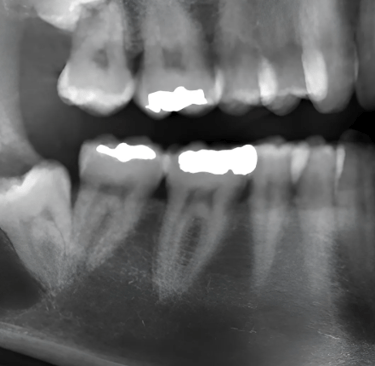

At smile center, our exams are completley free and include basic x-rays. Here we will point out exactly what you need, why, and how much and how many visits It would take.

We use 3D imaging and digital gscanners to plan precise extractions,

reducing swelling and healing time for better long-term results.